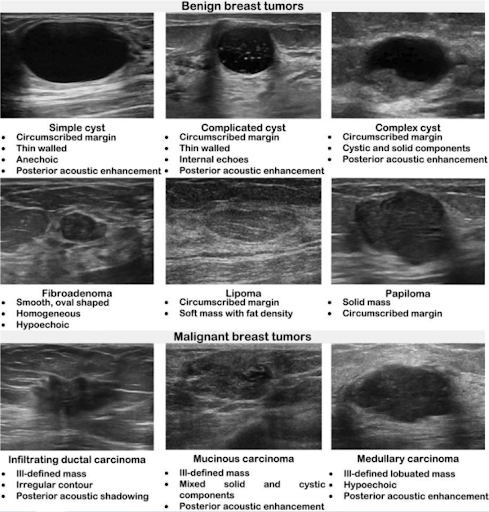

When performing breast ultrasound, describe the lesion using the following features (Malherbe 2024):

-

Shape: Oval, round or irregular

-

Position: Describe relative to a clock face

-

Orientation: Parallel or not parallel

-

Margin: Circumscribed or not, further characterized as indistinct, angular, microlobulated, or spiculated

-

Echo pattern: Anechoic, hyperechoic, complex cystic and solid, hypoechoic, isoechoic, heterogenous

Posterior features: No posterior features, posterior acoustic enhancement, posterior acoustic shadowing, or combined pattern

Most common benign morphologic features (Flory 2020):

-

Smooth and well-circumscribed margins

-

Hyperechoic, isoechoic, or mildly hypoechoic in echogenicity

-

Thin echogenic capsule or well-defined capsule border

-

Ellipsoid shape, wider than tall appearance

-

Macrolobulated; <3 lobulated margins

-

Posterior acoustic enhancement

Most common malignant morphologic features (Flory 2020, Vincent 2020):

-

Hypoechoic mass, on occasionally hyperechoic in appearance

-

Spiculated margins

-

Ill-defined borders, architectural distortion of surrounding soft tissue

-

Posterior acoustic shadowing

-

Taller than wide appearance

-

Presence of microcalcifications